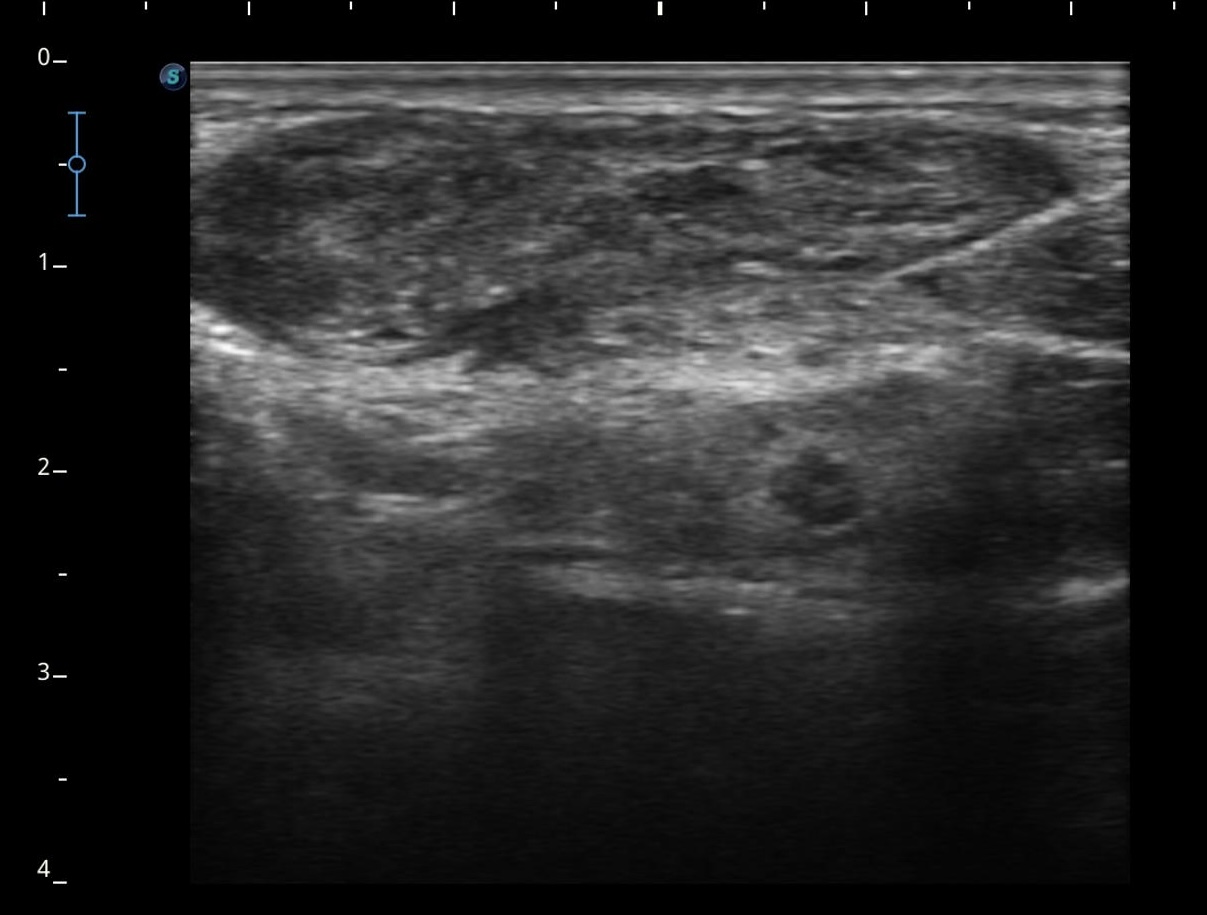

Se realiza ecografía clínica objetivándose ausencia de flujo en el interior de la luz, con imagen ecogénica en el interior compatible con trombo, no colapsándose a la presión con el transductor.

Sospechamos de trombosis venosa yugular externa (VYE). Se deriva a servicio de Urgencias para completar estudio.

Se realiza analítica de sangre (Dímero D 2029 ng/ml) y radiografía de tórax anodina. Se realiza eco-doppler cervical observándose trombosis de vena yugular externa izquierda al menos hasta su confluencia yugulosubclavia. Vena yugular izquierda no visualizada. Venas subclavia, axilar y braquiales izquierdas permeables sin datos de trombosis.

Se confirma nuestra sospecha diagnóstica: obstrucción total venosa central (OTVC) trombótica de la vena yugular externa.